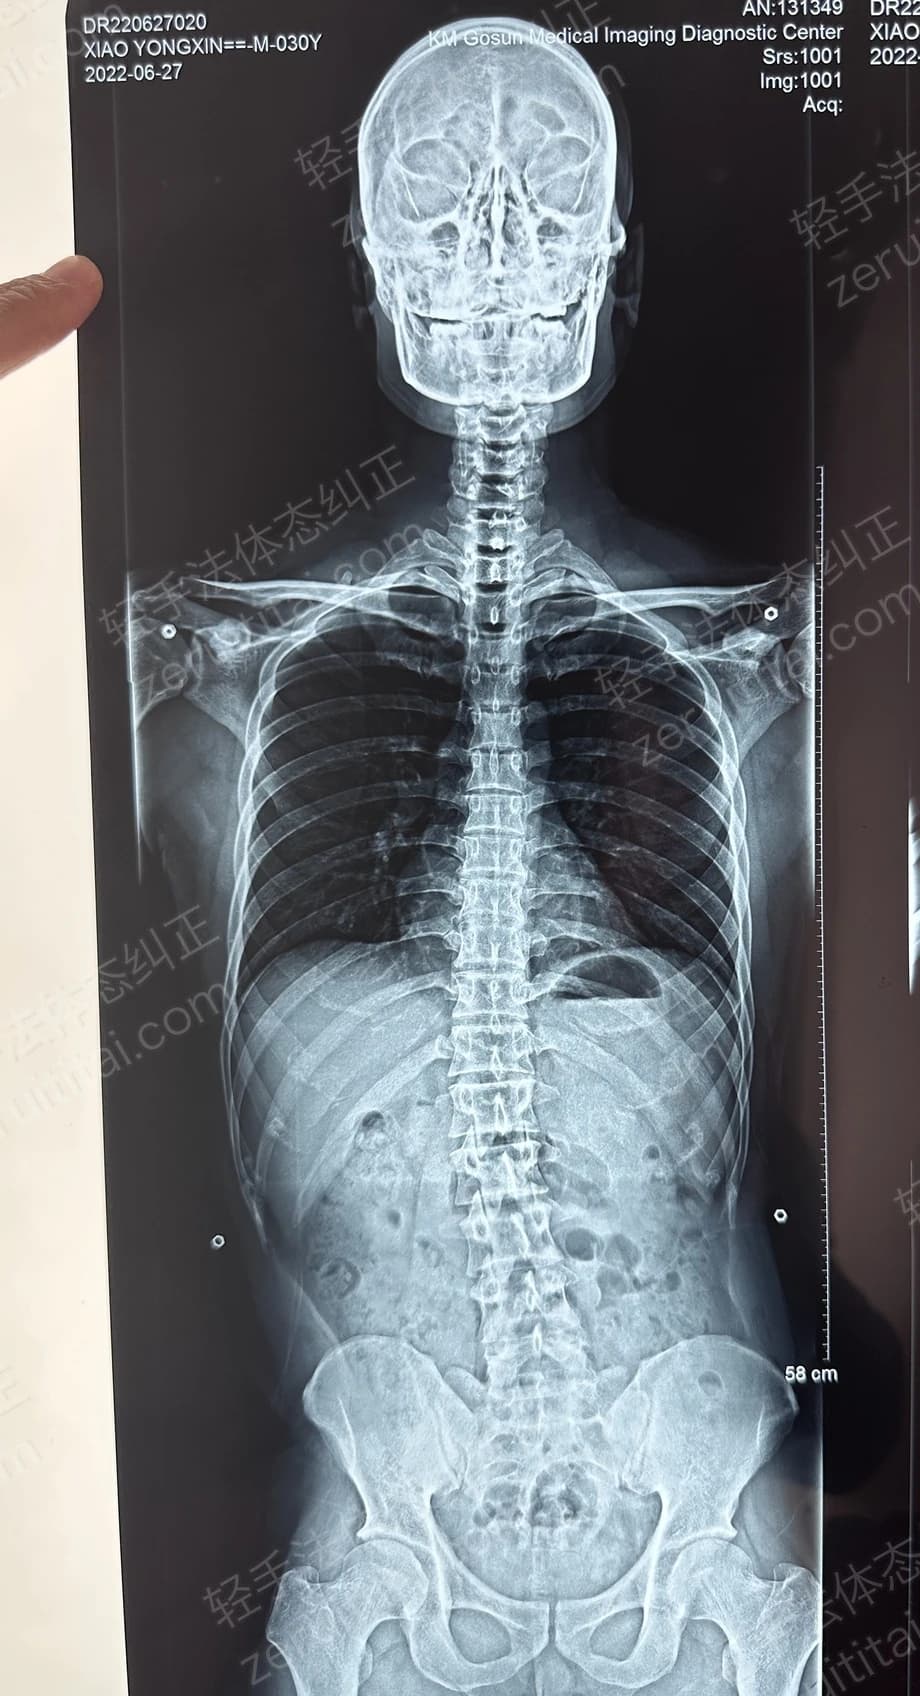

2022.06.27

第 1 次记录

第 1 次记录2022.06.27

正面 X 光